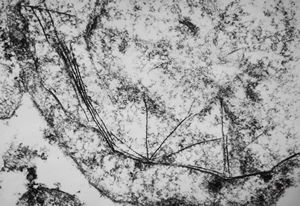

F,39y. | collagen and elastin - aorta

F,39y. | collagen, elastin and oxytalan microfibrils

F,45y. | collagen fibril - skin

F,29y. | collagen, elastin and oxytalan microfibrils - endomyocardial fibrosis